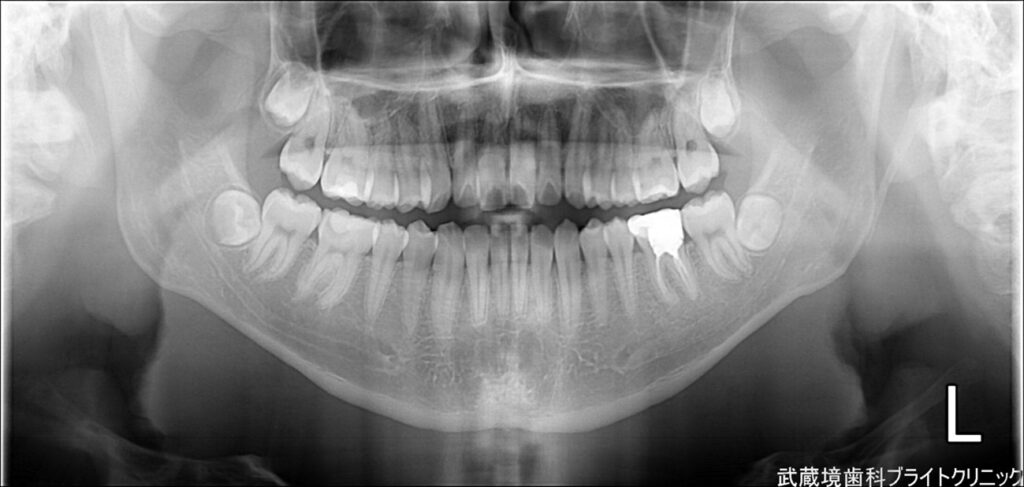

親知らずは抜いた方がいい場合が多いです。痛みがないからと放置しておくと、将来的に歯並びや噛み合わせに影響を与えたり、他の歯を圧迫したりすることがあります。

特に、親知らずが完全に生えない場合や、斜めに生えている場合は、早めに抜歯する方がリスクを避けられます。この記事では、親知らずを抜いた方がいい理由と、抜歯にかかる費用についても詳しく解説しますので、判断材料をしっかりとご確認いただけます。

親知らずが斜めに生えていたり、完全に生えなかったりすると、隣の歯を圧迫することがあります。これが長期的に続くと、歯並びや噛み合わせに影響を与え、矯正治療が無駄になったり、噛み合わせが不安定になることがあります。食事や会話に支障をきたすこともあるため、早めに抜歯することで将来的なトラブルを防ぐことができます。

親知らずが埋まっている場合

親知らずが完全に埋まっていると、歯茎の中で圧力がかかり、痛みや腫れを引き起こすことがあります。また、埋まった親知らずは歯科治療が難しく、感染症や膿が溜まるリスクがあります。放置しておくと、周囲の歯に悪影響を与えることがあるため、早期に抜歯することでトラブルを避けることができます。